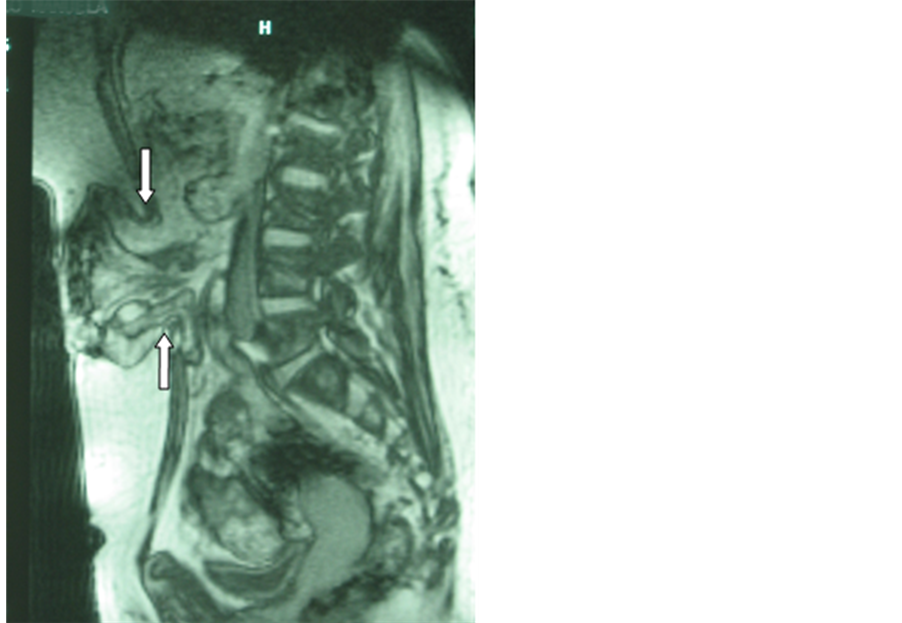

Preoperative MRI was very effective in showing the abdominal wall defects, not only in the axial position but in the sagittal view, allowing an appropriate evaluation of the hernia sac content, especially when the small bowel or colon were included. The evaluation of the presence and the extent of abdominal adhesions are very useful in surgery planning.

However the most important usefulness of the preoperative study was the possibility to get an accurately outline of the abdominal wall in the defect area in order to make a more effective treatment (Figure 1).

Figure 1. Preoperative MRI: sagittal view of a large incisional hernia. The arrows show the edges of the abdominal wall defect.